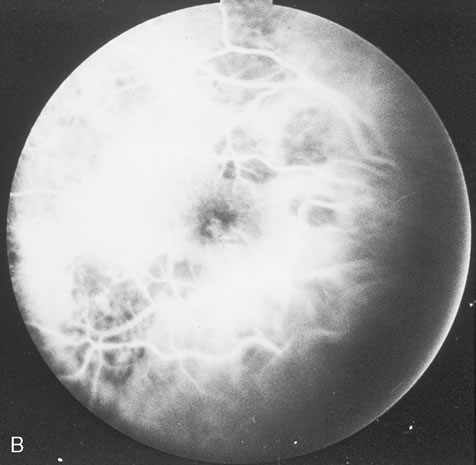

CMV retinitis is common in patients with AIDS. Perivascular granular white or yellowish infiltrates with hemorrhage are typical (Fig. 7). Minimal vitritis or anterior uveitis may be present. The posterior pole, including optic nerve, or peripheral retina may be involved. Optic neuritis may be retrobulbar. Resolution of retinal lesions reveals local retinal atrophy and pigment dispersion. Iridocyclitis may occur secondary to infection of ciliary processes. CMV retinitis in patients with AIDS is considered a poor prognostic sign in terms of life expectancy. Congenital CMV infection may also cause retinitis, as well as anterior uveitis, cataract, and optic atrophy. New foci of retinochoroiditis can develop in later years of congenital infection, and such infants require periodic reexamination as long as virus is shed in the urine.

Fig. 7. Cytomegalovirus retinitis in a patient with aquired immune deficiency syndrome (AIDS). Note the large area of retinal necrosis along with the perivascular distribution of the lesions.